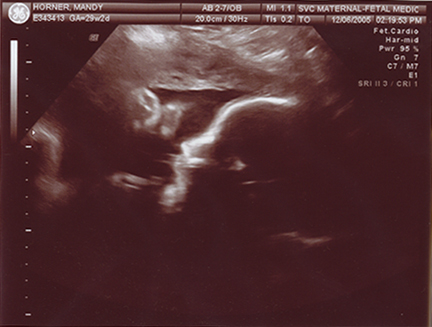

December 10, 2005 - Mandy has gone in for her doctor's appointments, and Evan is doing very well! He is a little over 2 pounds, and he is at 29 to 30 weeks! He is a very active little fellow, Manders can definately tell you that! We plan to go to Sioux Falls at least twice a week when Mandy is at 32 wks. She will undergo NoStress tests. Mandy has a lot better details for you than I would! She always keeps up with Evan on her LiveJournal site!